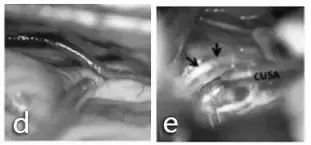

手术入路和体位:仰卧位,通过左侧颞下入路进行手术。事先放置腰部引流管,并在暴露期间释放脑脊液以放松大脑并避免颞叶损伤。术中完整保留Labbé静脉(d图),通过切开其周围的蛛网膜层而与颞叶分离。e图表示使用CUSA刀切除肿瘤,同时保护邻近的滑车神经(箭头指示)。